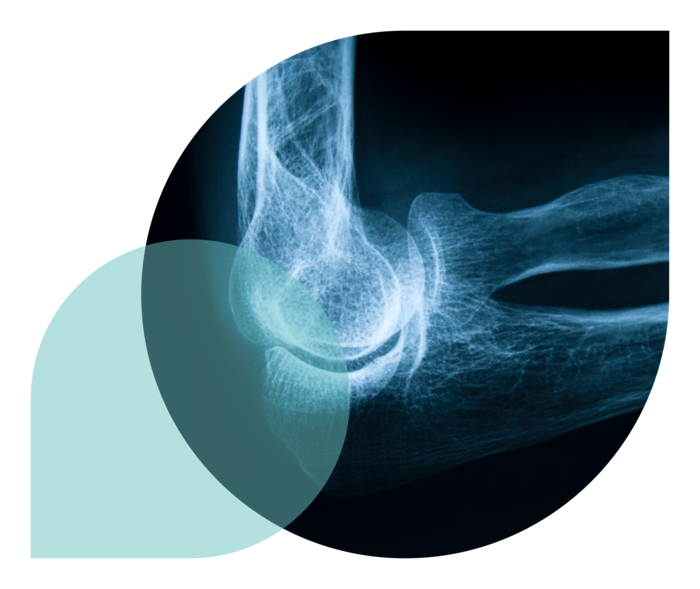

Die rheumatoide Arthritis,

abgekürzt RA,

ist die häufigste

entzündlich-rheumatische

Gelenkerkrankung.

Die RA ist nicht ansteckend, chronisch (in den meisten Fällen bleibt sie ein Leben lang) und verläuft in Schüben, die sich ohne Therapie immer mehr verstärken und schließlich die Gelenke schädigen. Schmerzen in den Gelenken und ein zunehmender Funktionsverlust sind die Folge. Die rheumatoide Arthritis ist eine systemische Krankheit, betrifft also den ganzen Körper.